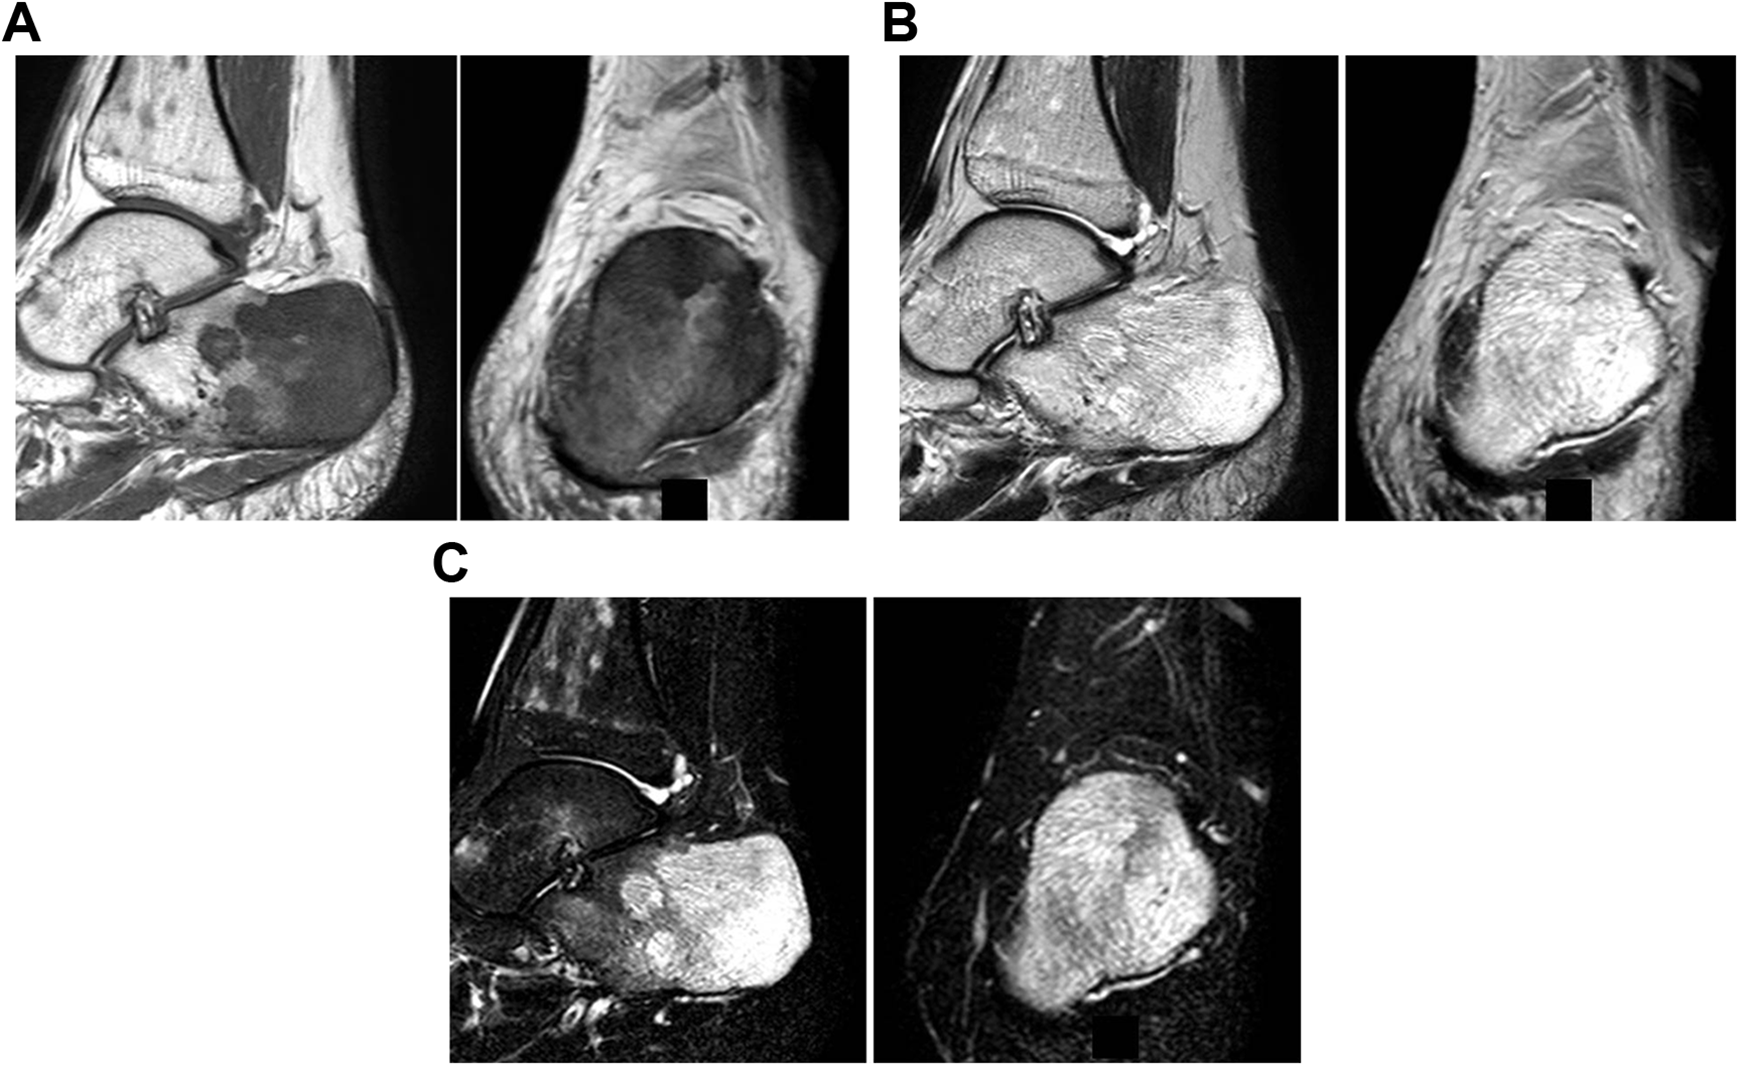

Hematological tests showed pancytopenia (Table 1). X-ray and computed tomography (CT) showed no evidence of destruction of the trabeculae in the left calcaneus (Figure 1 and Figure 2A,B). However, on MRI, the middle to posterior part of the left calcaneus showed low intensity in T1-weighted image, high intensity in T2-weighted image, and high intensity in short-TI inversion recovery (Figure 3A-C). Taking all clinical physical findings into consideration, we suspected that the lesion of the left calcaneus was either a lymphoproliferative tumor, such as leukemia, multiple myeloma, or lymphoma, or a trabecular type bone metastatic tumor, such as small cell carcinoma.

Magnetic resonance images of the left calcaneus, (A) sagittal or coronal T1-weighted images demonstrating abnormal hypointense signal of the visualized bone marrow. (B) Sagittal or coronal T2-weighted images demonstrating abnormal hyperintense signal of the visualized bone marrow. (C) Sagittal or coronal short-TI inversion recovery images demonstrating abnormal hyperintense signal of the visualized bone marrow.

MRI of the affected calcaneus of this present case showed low signal intensity signal on T1-weighted and high signal intensity on T2-weighted images. Similarly, lymphoproliferative tumors, such as leukemia, multiple myeloma, and lymphoma, ordinarily show low signal intensity in bone marrow on T1-weighted and high signal intensity in bone marrow images. 8 Metastases of some tumors, such as small cell carcinoma, which grow between trabeculae within marrow without causing gross trabecular or cortical destruction, also typically show low signal intensity on T1-weighted and high signal intensity on T2-weighted images in bone marrow images. 8 Because these findings were consistent with this case, open biopsy could not be avoided to distinguish GTBM from lymphoproliferative tumors or trabecular-type bone. It is important for foot and ankle surgeons to be aware of GTBM as a possibility in the differential diagnosis when they encounter patients with AN and these MRI findings in the calcaneus.